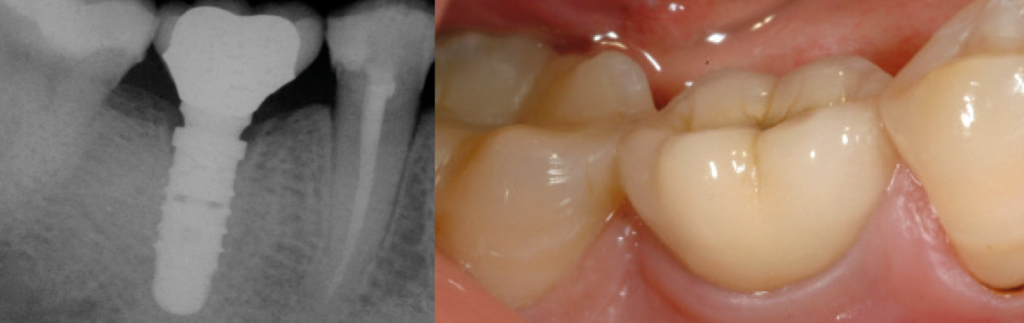

Il secondo fattore chiave per il mantenimento dell’estetica nel tempo è il SIGILLO MICROBIOLOGICO della connessione impianto-moncone. Grazie alla connessione a cono Morse Leone, i tessuti perimplantari vengono disturbati meno, rendendo possibili eccellenti guarigioni e il mantenimento dei tessuti duri e molli negli anni (Figg. 3 – 5).

Fig. 5a – Alla consegna

Fig. 5b – Follow up a 14 anni. Mantenimento dei tessuti negli anni